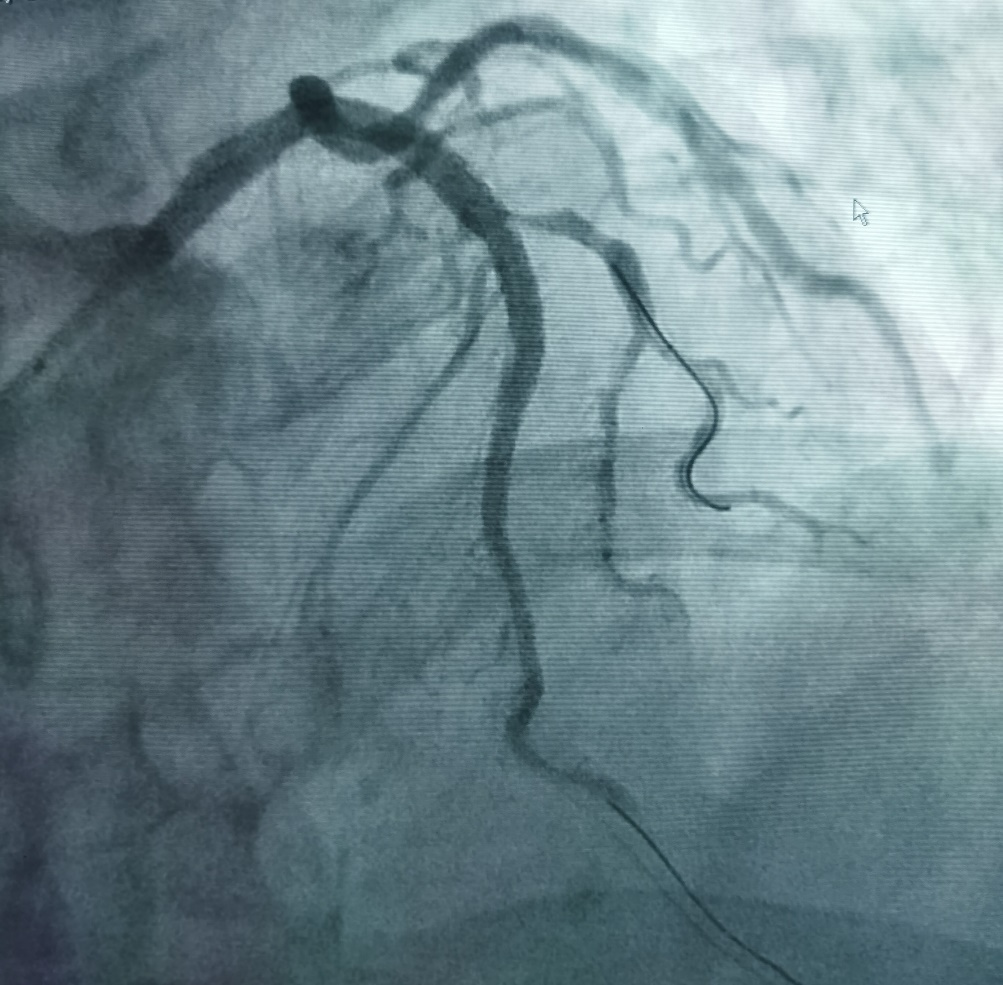

患者吴先生,68岁,有吸烟史20年,高血压史20年,持续胸闷1年,1月前剧烈活动后出现胸闷,持续数小时可自行缓解,入院后诊断为不稳定型心绞痛。冠脉造影显示冠脉左前降支开口可见50%狭窄,近端可见95%偏心狭窄,局部瘤样扩张,可见钙化影(图1),此种情况极易造成支架膨胀不全。据此杨清教授和徐绍鹏教授果断选择3.0 x 12mm Shockwave IVL冲击波球囊对近段钙化病变进行4个周期40个脉冲的预处理(图2),而后植入支架,达到了理想的支架膨胀结果(见图3)。

图1 患者冠脉造影图像:红色弧线区域血管可见明显钙化影(未应用造影剂X线下即可见血管轮廓)